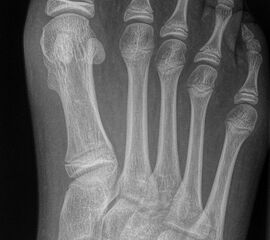

DMMO/DMDO (Distale Minimalinvasive Metatarsale Osteotomie/Distale Minimalinvasive Diaphysäre Osteotomie)

Die Indikation für eine DMMO oder DMDO (Distale Minimalinvasive Metatarsale Osteotomie/Distale Minimalinvasive Diaphysäre Osteotomie) beim Kind mit wachsendem Skelett ist nicht die klassische Metatarsalgie des Erwachsenen. In der Kinderorthopädie kann eine gute Indikation für die DMMO oder für eine DMDO der Ballen-Hohl-Fuß mit Metatarsalgie sein. Wird z. B. bei einer frühen Hohlfußkorrektur das Metatarsale I für eine bessere Rückfußeinstellung extendiert und zur Aufhebung der Extensorensubstitution die Sehne des M. tibialis posterior transferiert, kann sich im Verlauf eine Dysbalance der Metatarsalia entwickeln und eine Metatarsalgie unter II-IV auftreten. Mit einer DMDO werden die Köpfchen II-IV effektiv angehoben und die Beschwerden gebessert (Abb. 17 und 18).

Abb. 18 a-b: Beispiel einer DMDO beim Hohlfuß d.p. (dorso-plantare) Ansicht (a) und schräge Ansicht (b).